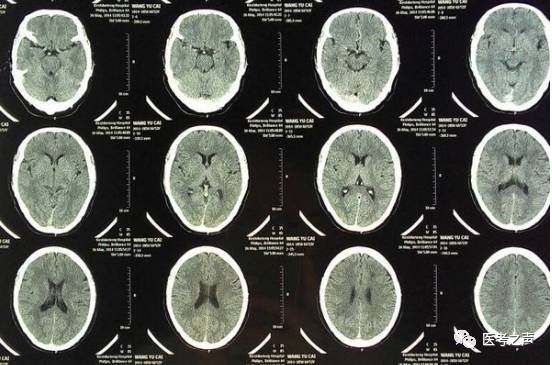

CT

像把面包切片看

CT意为X线计算机断层摄影,是用X线束对人体某部进行断层扫描,获得人体被检部的断面或立体图像。CT可以提供人体被检查部位的完整三维信息,可使器官和结构清楚显影,清楚地显示病变。就像把一片面包切成片来看。优点是可以分层看,经计算后可以显示出更多的组织信息。